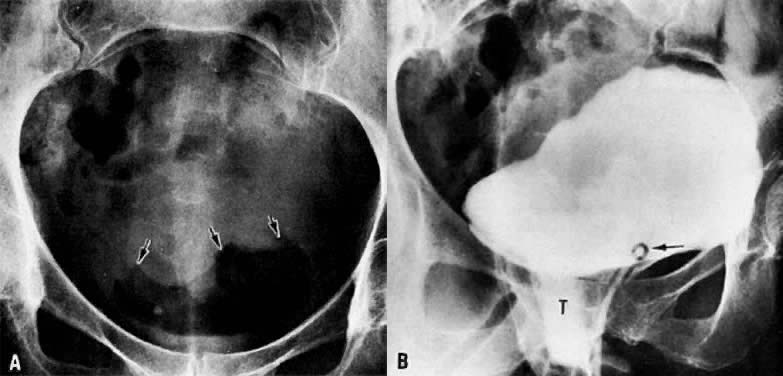

Air in the bladder seen on plain film examination (Fig. 40A) may indicate a vesicovaginal fistula. Placing a tampon in the vagina before a cystogram is an effective method of demonstrating this fistula (Fig. 40B). The contrast medium instilled into the bladder fills the tampon as it flows through the fistula, and an oblique projection shows the opacified vaginal tampon. Contrast medium absorbed by the tampon can also be seen after drainage of the bladder. A colon examination can demonstrate a vesicovaginorectal fistula. Barium introduced into the rectum fills the vaginal vault and urinary bladder (Fig. 41). MRI and ultrasound are more accurate in assessing bladder wall infiltration by tumor (see Fig. 17C, Fig. 18, Fig. 20, and Fig. 24A).

Fig. 40. A. Plain film of abdomen. Air-filled bladder in a patient with vesicovaginal fistula. Dome of bladder is outlined with arrows. B. Cystogram. Contrast medium fills the bladder and runs onto the vaginal tampon ( T) inferior to the bladder and posterior to the Foley catheter ( arrow ).